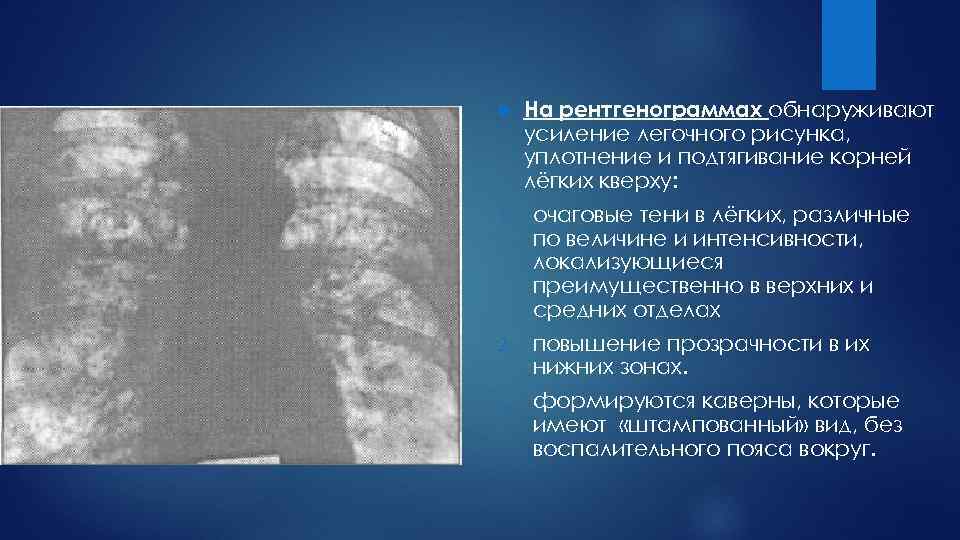

Фотографии, демонстрирующие обнаруженное усиление легочного рисунка

Раздел: Фотодневник открытий